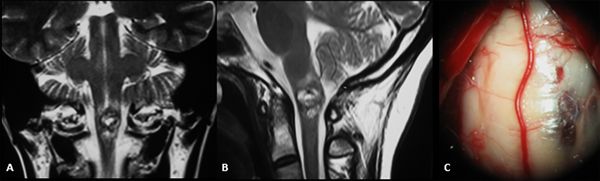

En resonancia magnética (RM) cerebral podemos observar lesiones heterogéneas con intensidades variables en su interior, con zonas hiperintensas secundarias a la metahemoglobina, y un halo hipointenso periférico relacionados con la presencia de hemosiderina. La clasificación por imágenes de Zabramski permite correlacionar los hallazgos en resonancia con el estadio de la enfermedad, desde un tipo I en una hemorragia subaguda, tipo II con hemorragias y trombosis intralesionales en distintas fases de degradación (popcorn sign) hasta una fase III con hemorragia crónica, y un tipo IV relacionada con cavernomas pequeños y telangiectasias. De igual forma, la RM permite valorar la localización detallada de la lesión y su relación con la superficie pial o ventricular, aspecto de importancia en la determinación de la vía de acceso (Figura 1).1,7,11

Figura 1: RM ponderación en T2, proyección coronal (A) y sagital (B) donde se evidencia cavernoma Zabramski II localizado a nivel del bulbo raquídeo. Imagen intraoperatoria de mismo paciente (C) con evidencia de lesión en contacto con superficie pial del tronco cerebral.